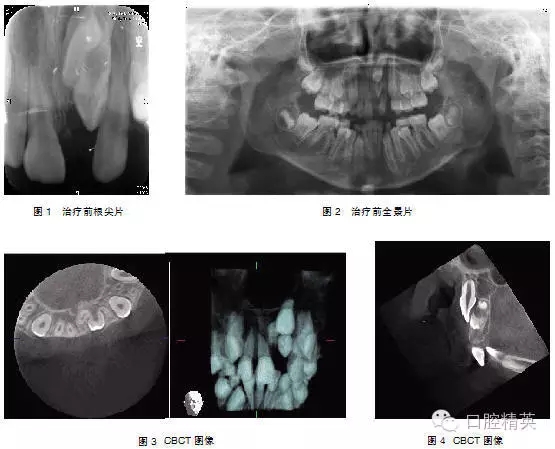

典型病例1: 患者,男,10歲,因左上前門牙未萌出于2009年10月來上海第九人民醫(yī)院預防、兒童口腔科就診。檢查: |1未萌,1| 全萌,1|2之間間隙為4mm。牙片及全景片示: |1骨內埋伏,1| 2之間有埋伏多生牙,多生牙與 |1的重疊,不能清晰顯示多生牙和 |1在頜骨中的具體方位及相關關系(圖1-2),采用CBCT掃描后,圖像能清晰顯示多生牙和 |1的形態(tài)、大小、數目、牙根發(fā)育情況、在頜骨中具體位置、萌出方向及相互關系(圖3-4),經手術證實情況與CBCT圖像顯示完全一致,手術拔除多生牙, |1作外科開窗術+正畸牽引治療。

3.1 準確的定位 上頜前牙區(qū)埋伏牙在頜骨內變異較大,臨床上根據埋伏阻生牙的發(fā)病原因、阻生位置和發(fā)育情況的不同,治療方案也不同,采用正畸牽引助萌或拔除方法。對埋伏阻生牙患者應首先拍攝常規(guī)根尖片、全景片或頭顱側位片等,對明確診斷但不能清晰顯示上頜前牙區(qū)埋伏牙具體方位的病例加攝CBCT片,準確地顯示埋伏牙形態(tài)、大小、數目、牙根發(fā)育情況、在頜骨中具體位置、萌出方向及其與鄰牙的關系,以便關系到最佳治療方案的確定;手術時間的長短、進路方向、暴露范圍及確定正畸附件附著點和牽引方向、創(chuàng)傷的大小及和提示治療預期效果(典型病例1、2)。